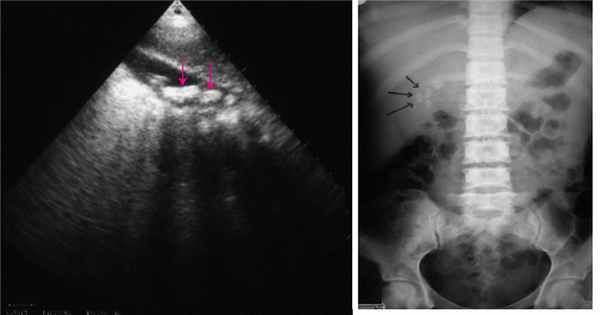

Дивертикулы желудка обычно обнаруживаются случайно при эндоскопических исследованиях или визуализациях (например, в исследованиях верхних отделов желудочно-кишечного тракта с барием, КТ с контрастированием). Преобладающее местоположение –проксимальная часть желудка вдоль большой кривизны. Размер дивертикулов колеблется от 1 до 3 см в диаметре. Дивертикулы желудка образованы выпячиванием слизистой оболочки желудка через мышечный слой, но при этом не сквозь всю стенку желудка (возможно, из-за толщины мышечных слоев), поэтому они называются интрамуральными, или частичными дивертикулами.

Наиболее часто дивертикулы локализуются в кардиальном и субкардиальном отделах желудка (почти в 80 % случаев), особенно на задней стенке. Значительно реже дивертикулы располагаются по большой кривизне (около 8%) и в антральном отделе (около 10%), очень редко (около 2%) - на передней стенке тела и по малой кривизне (в области средней и нижней третей желудка).

Дивертикулы имеют грушевидную, более редко - овальную или круглую форму. Размер ДЖ - в основном небольшой (2-3 см в диаметре), однако встречаются и ДЖ более крупных размеров (6-7 см и больше). В дивертикулах малых размеров обычно определяется мышечная оболочка, в средних ДЖ зачастую выявляются только отдельные мышечные пучки, в крупных - мышечная оболочка, как правило, отсутствует.